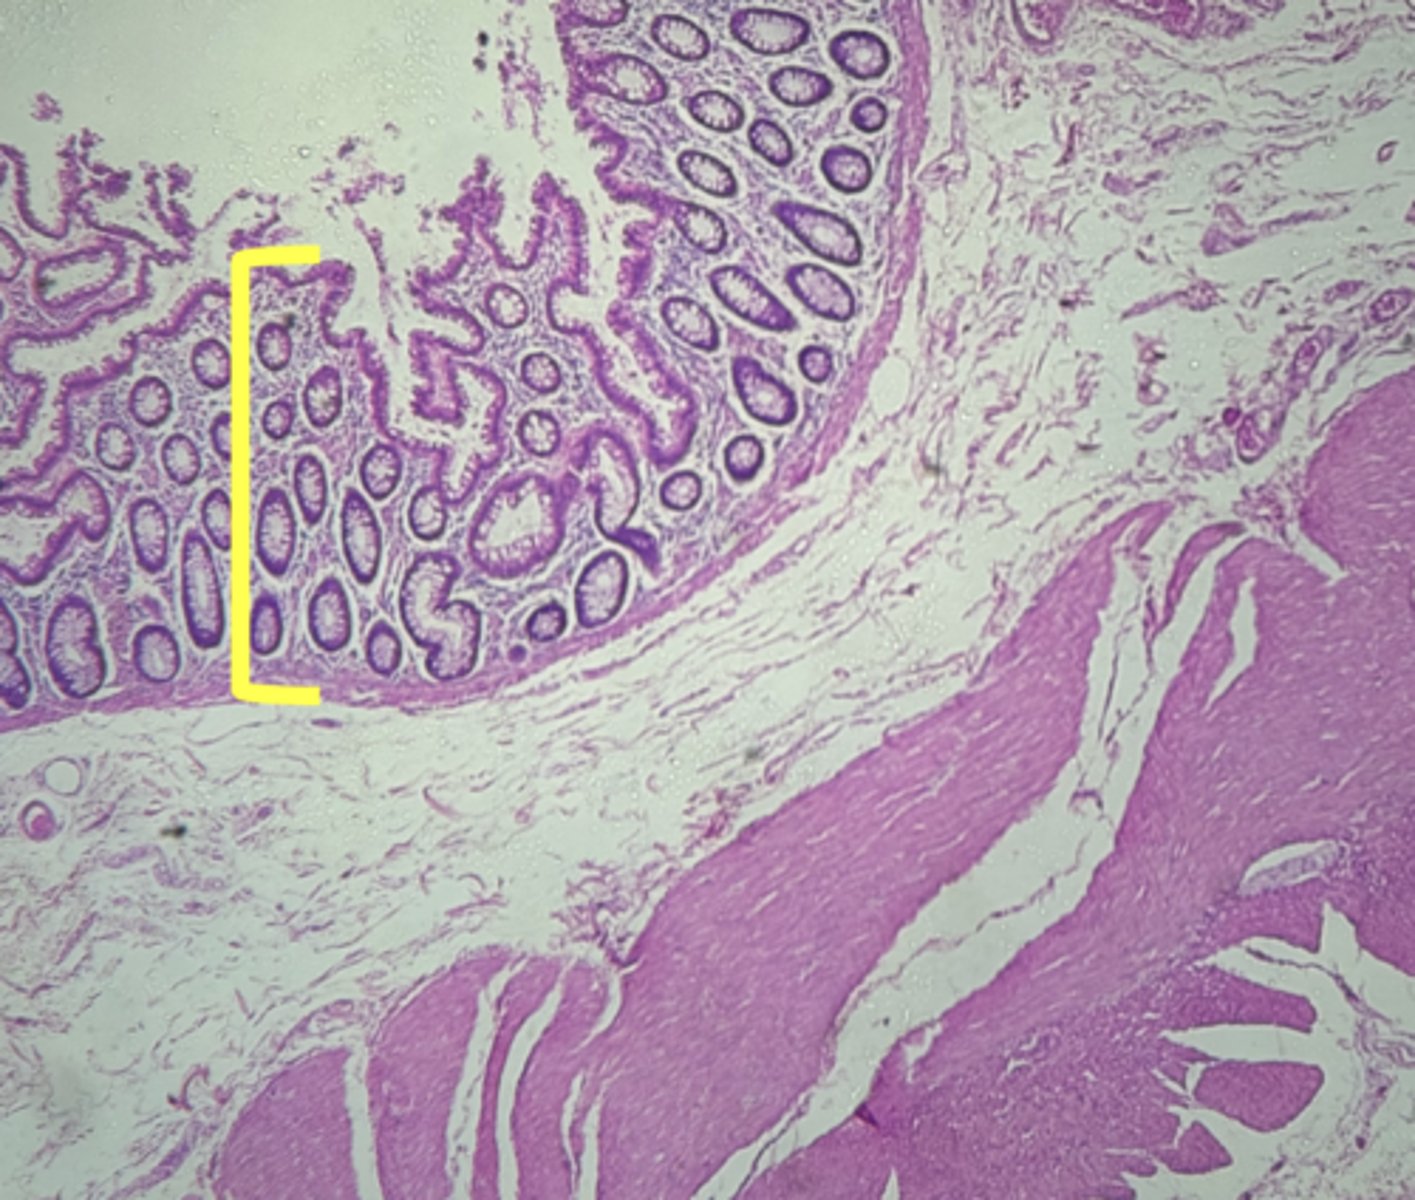

stomach

name the tissue

mucosa

(stomach)

submucosa

simple columnar epithelium

gastric pits (KEY CHARACTERISTIC)

gastric glands (KEY CHARACTERISTIC)

Lamina propria

muscularis mucosae